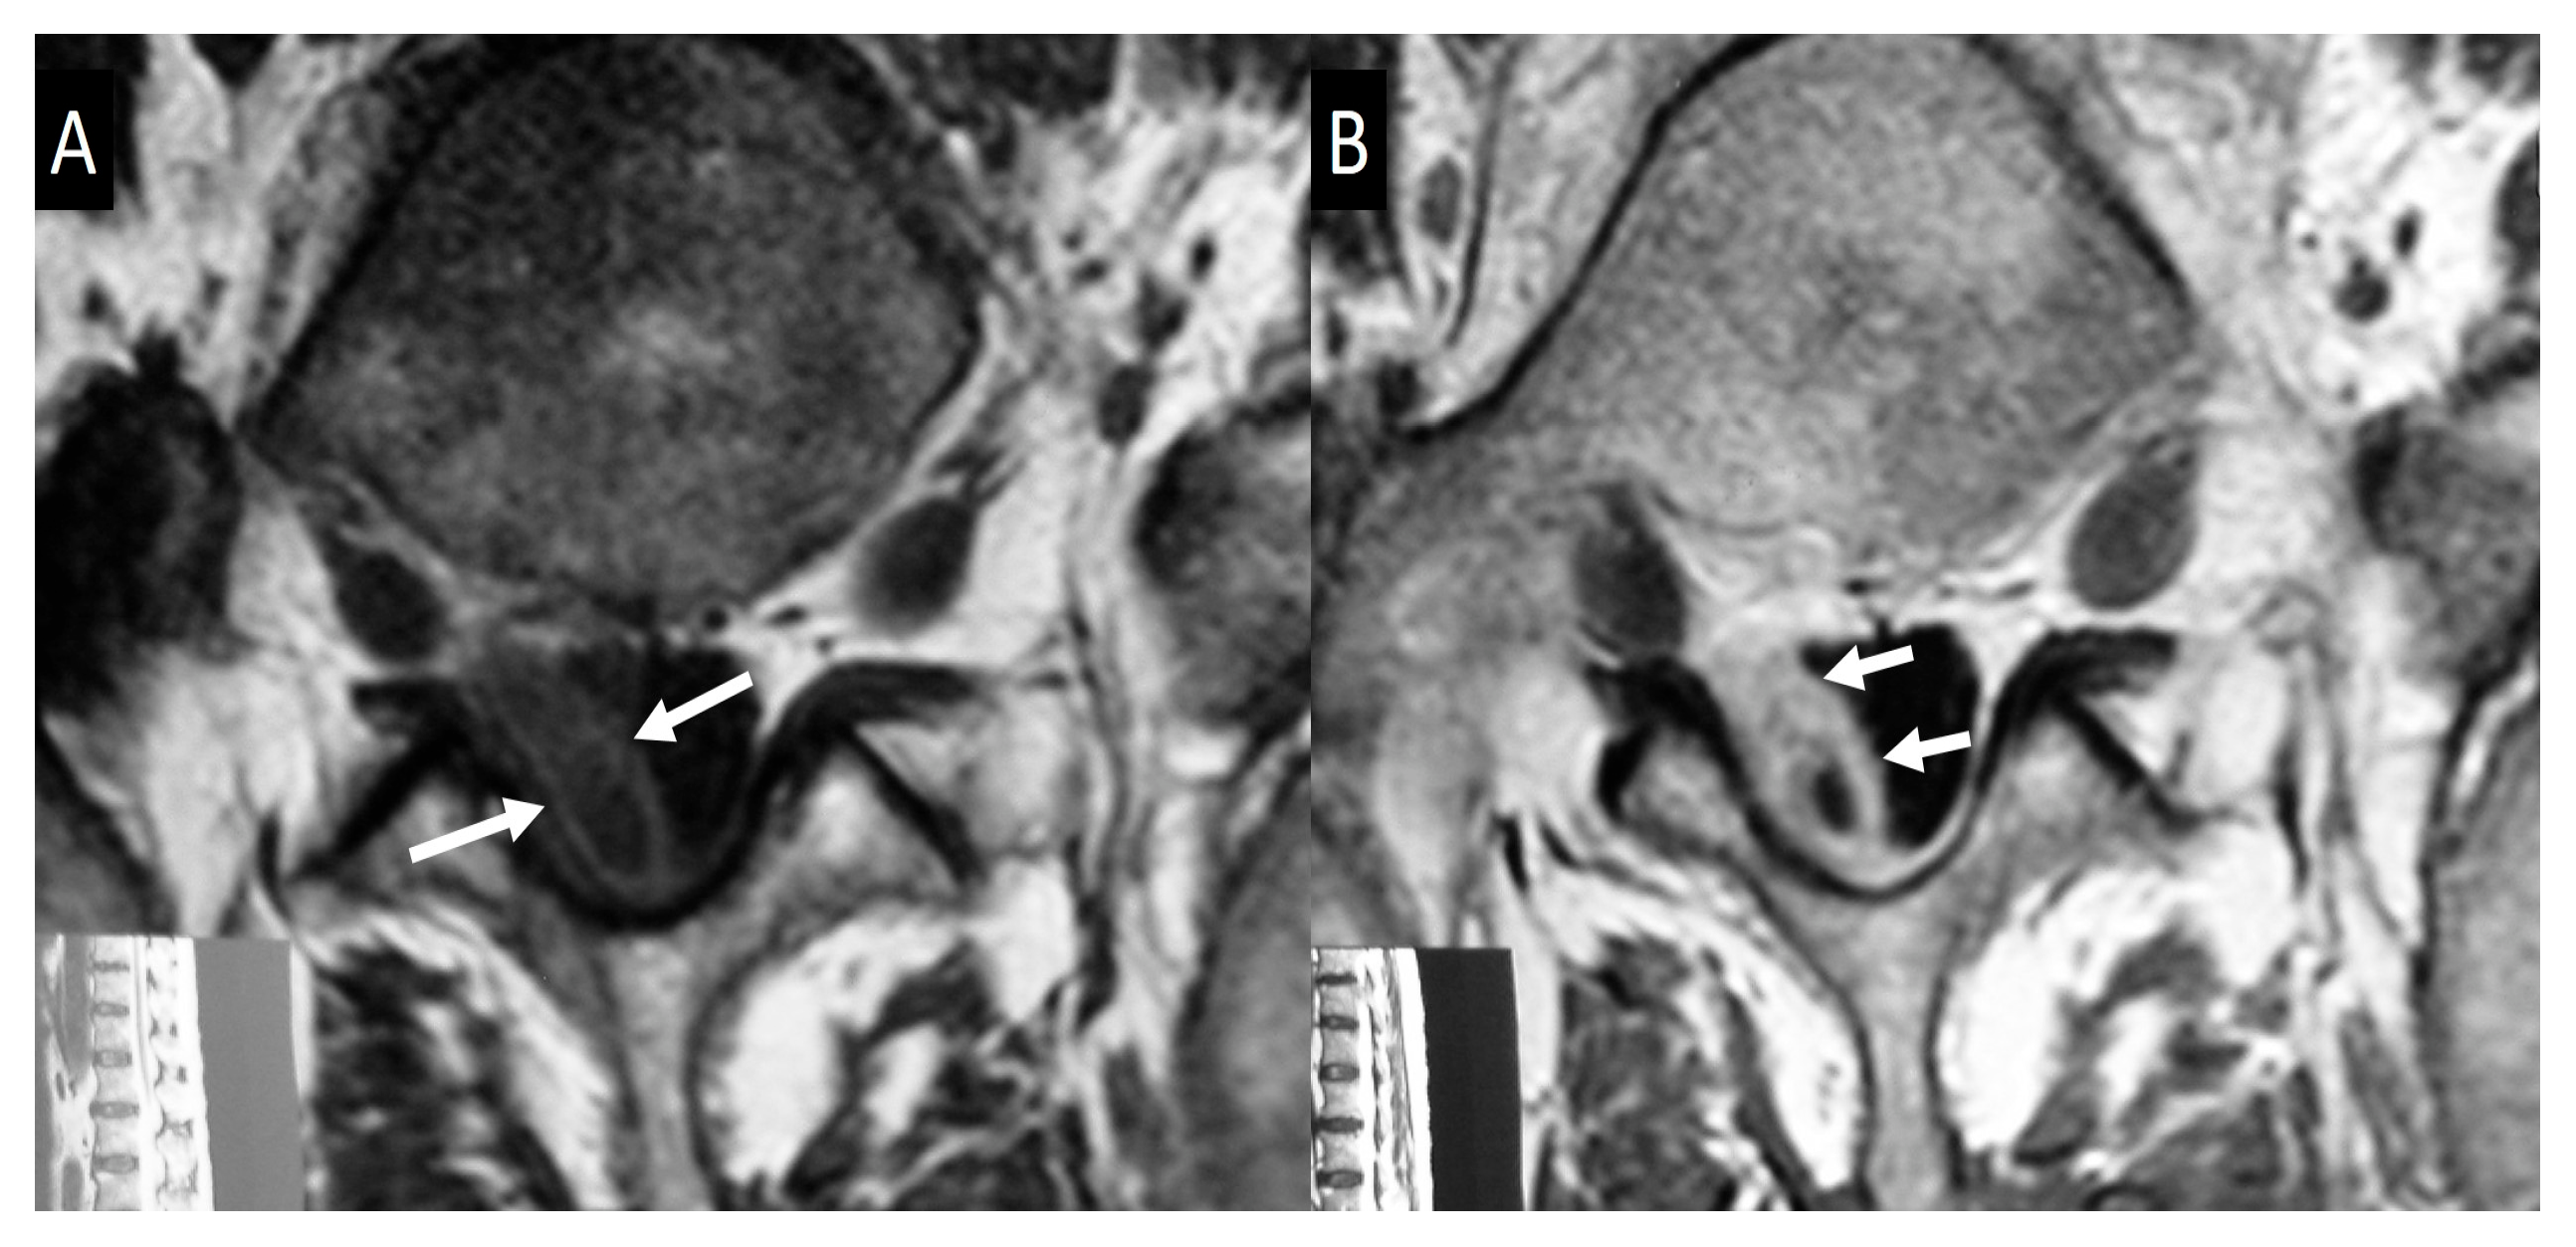

- Bozgeyik, Z.; Ozdemir, H.; Demirdag, K.; Ozden, M.; Sonmezgoz, F.; Ozgocmen, S. Clinical and MRI findings of brucellar spondylodiscitis. Eur. J. Radiol. 2008, 67, 153–158. [Google Scholar] [CrossRef]

- Bozgeyik, Z.; Aglamis, S.; Bozdag, P.G.; Denk, A. Magnetic resonance imaging findings of musculoskeletal brucellosis. Clin. Imaging 2014, 38, 719–723. [Google Scholar] [CrossRef]

- Ozaksoy, D.; Yucesoy, K.; Yucesoy, M.; Kovanlikaya, I.; Yuce, A.; Naderi, S. Brucellar spondylitis: MRI findings. Eur. Spine J. 2001, 10, 529–533. [Google Scholar] [CrossRef] [PubMed]

- Harman, M.; Unal, O.; Onbasi, K.T.; Kiymaz, N.; Arslan, H. Brucellar spondylodiscitis: MRI diagnosis. Clin. Imaging 2001, 25, 421–427. [Google Scholar] [CrossRef] [PubMed]

- Chelli Bouaziz, M.; Ladeb, M.F.; Chakroun, M.; Chaabane, S. Spinal brucellosis: A review. Skelet. Radiol. 2008, 37, 785–790. [Google Scholar] [CrossRef]

- Sharif, H.S.; Clark, D.C.; Aabed, M.Y.; Haddad, M.C.; al Deeb, S.M.; Yaqub, B.; al Moutaery, K.R. Granulomatous spinal infections: MR imaging. Radiology 1990, 177, 101–107. [Google Scholar] [CrossRef]

- al-Shahed, M.S.; Sharif, H.S.; Haddad, M.C.; Aabed, M.Y.; Sammak, B.M.; Mutairi, M.A. Imaging features of musculoskeletal brucellosis. Radiographics 1994, 14, 333–348. [Google Scholar] [CrossRef]

- Guo, H.; Lan, S.; He, Y.; Tiheiran, M.; Liu, W. Differentiating brucella spondylitis from tuberculous spondylitis by the conventional MRI and MR T2 mapping: A prospective study. Eur. J. Med. Res. 2021, 26, 125. [Google Scholar] [CrossRef]

- Li, W.; Zhao, Y.H.; Liu, J.; Duan, Y.W.; Gao, M.; Lu, Y.T.; Yao, L.; Li, S.L. Imaging diagnosis of brucella spondylitis and tuberculous spondylitis. Zhonghua Yi Xue Za Zhi 2018, 98, 2341–2345. [Google Scholar] [CrossRef]